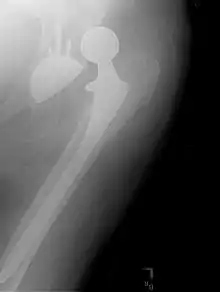

Prothèse totale de hanche

Une prothèse totale de hanche (PTH) est un dispositif articulaire interne qui vise à remplacer l'articulation de la hanche et lui permettre un fonctionnement quasi normal, en tout cas permettant la marche.

Choix de l'implant

Il y a différents types d'implant :